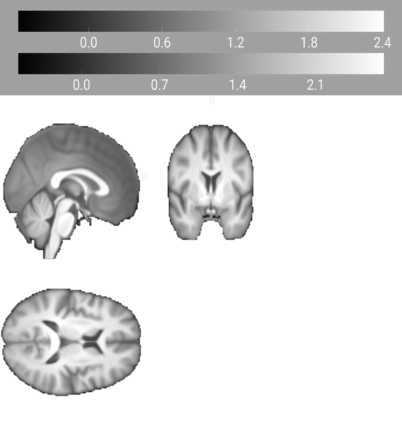

Our knowledge of the organisation of the human brain at the population-level is yet to translate into power to predict functional differences at the individual-level, limiting clinical applications, and casting doubt on the generalisability of inferred mechanisms. It remains unknown whether the difficulty arises from the absence of individuating biological patterns within the brain, or from limited power to access them with the models and compute at our disposal. Here we comprehensively investigate the resolvability of such patterns with data and compute at unprecedented scale. Across 23 810 unique participants from UK Biobank, we systematically evaluate the predictability of 25 individual biological characteristics, from all available combinations of structural and functional neuroimaging data. Over 4526 GPU hours of computation, we train, optimize, and evaluate out-of-sample 700 individual predictive models, including fully-connected feed-forward neural networks of demographic, psychological, serological, chronic disease, and functional connectivity characteristics, and both uni- and multi-modal 3D convolutional neural network models of macro- and micro-structural brain imaging. We find a marked discrepancy between the high predictability of sex (balanced accuracy 99.7%), age (mean absolute error 2.048 years, R2 0.859), and weight (mean absolute error 2.609Kg, R2 0.625), for which we set new state-of-the-art performance, and the surprisingly low predictability of other characteristics. Neither structural nor functional imaging predicted psychology better than the coincidence of chronic disease (p<0.05). Serology predicted chronic disease (p<0.05) and was best predicted by it (p<0.001), followed by structural neuroimaging (p<0.05). Our findings suggest either more informative imaging or more powerful models are needed to decipher individual level characteristics from the human brain.